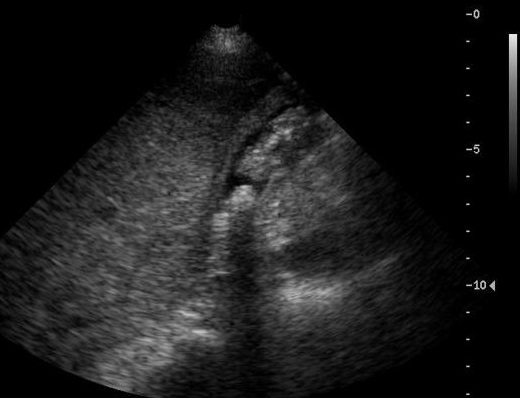

Image echographique de adenocarcinoma vesiculaire

: C'est image de masse isoechogene intraluminal a bord

irregulier , image de epaissisement de la paroi vesiculaire

et de deplacement de la vesicule biliaire avec grand calcul

vesiculaire . Image TDM et